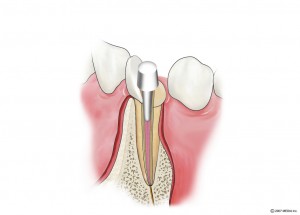

術前

インプラント挿入

土台装着

被せ物装着

同パノラマ写真

被せ物装着後歯肉の盛り上がり